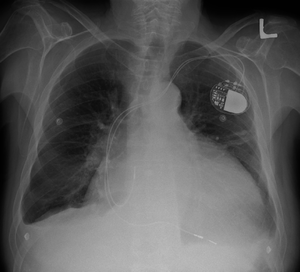

| Cardiomegaly on chest X-ray and a pacemaker | |

1. Chest X-Ray: X-ray images help see the condition of the lungs and heart. If the heart is enlarged on an X-ray, other tests will usually be needed to find the cause.